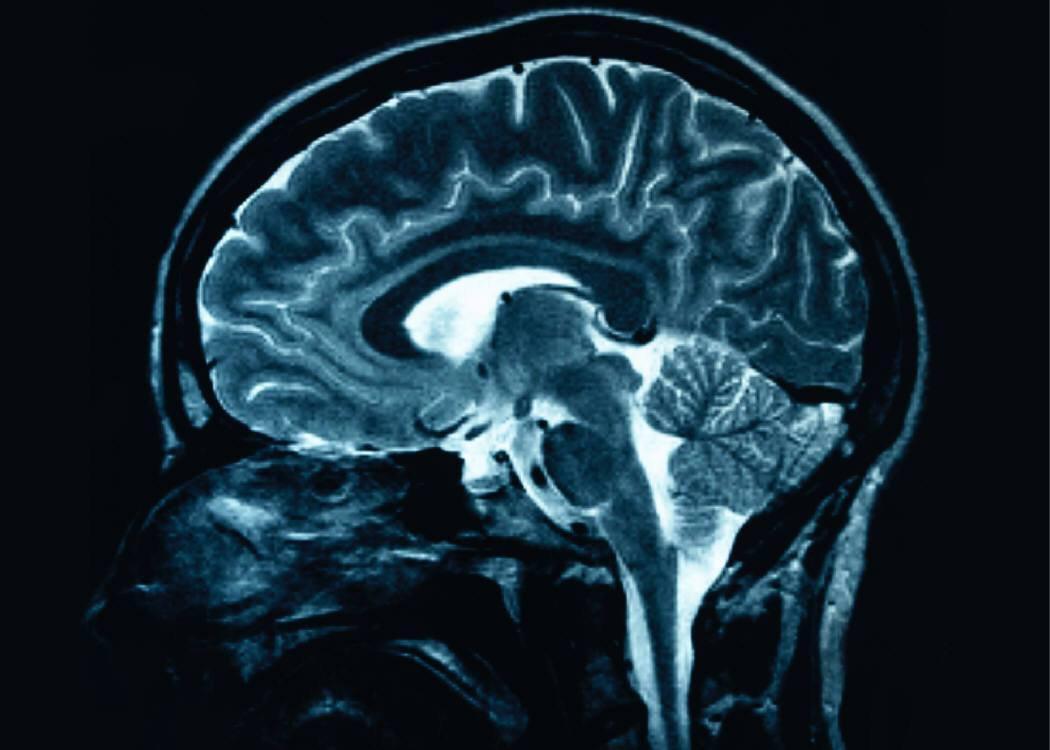

Brain

Is your brain getting smaller?

Your brain may be getting smaller according to a recent study published in the journal, “Neurology” (Vogiatzoglu A, et al, 2008). The good news is that you can prevent it by taking Vitamin B 12. The study cited here involved volunteers between the ages of 61 and 87 years who were free of...